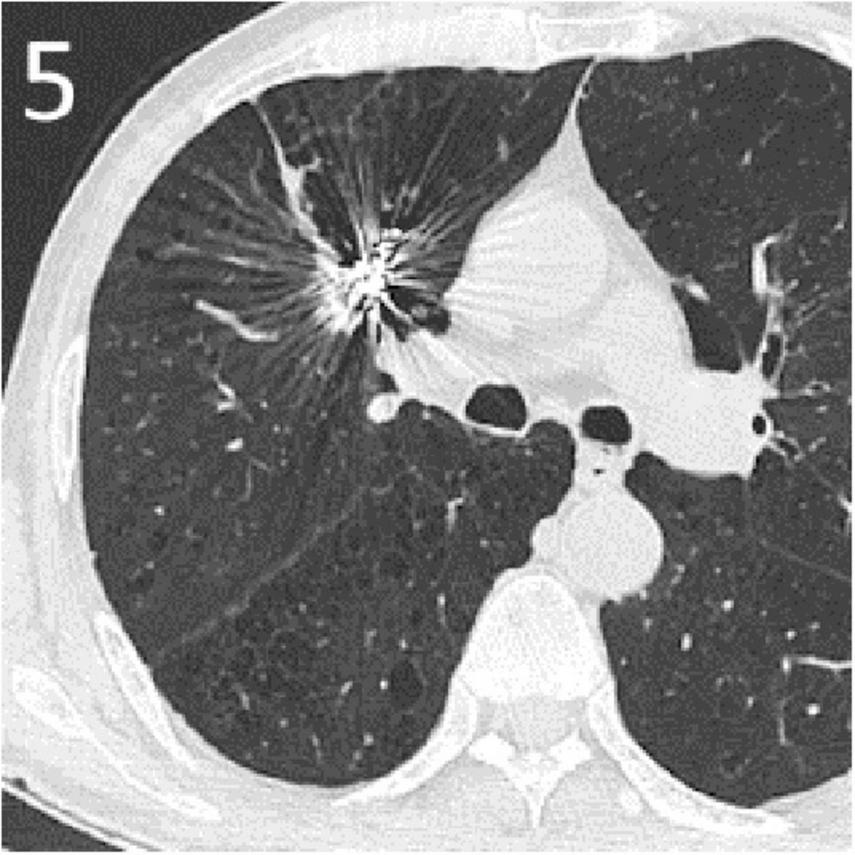

The patient experienced no active bleeding postoperatively, and follow-up over 6 months showed no recurrence of hemoptysis. Computed tomography (CT) scan 3 months post-embolization showed absorption of the tumor cavity with significant tumor reduction (Figure 5). Informed consent has been obtained for this report.

FIGURE 5

A CT scan 3 months post-embolization showed absorption of the tumor cavity with significant tumor reduction.